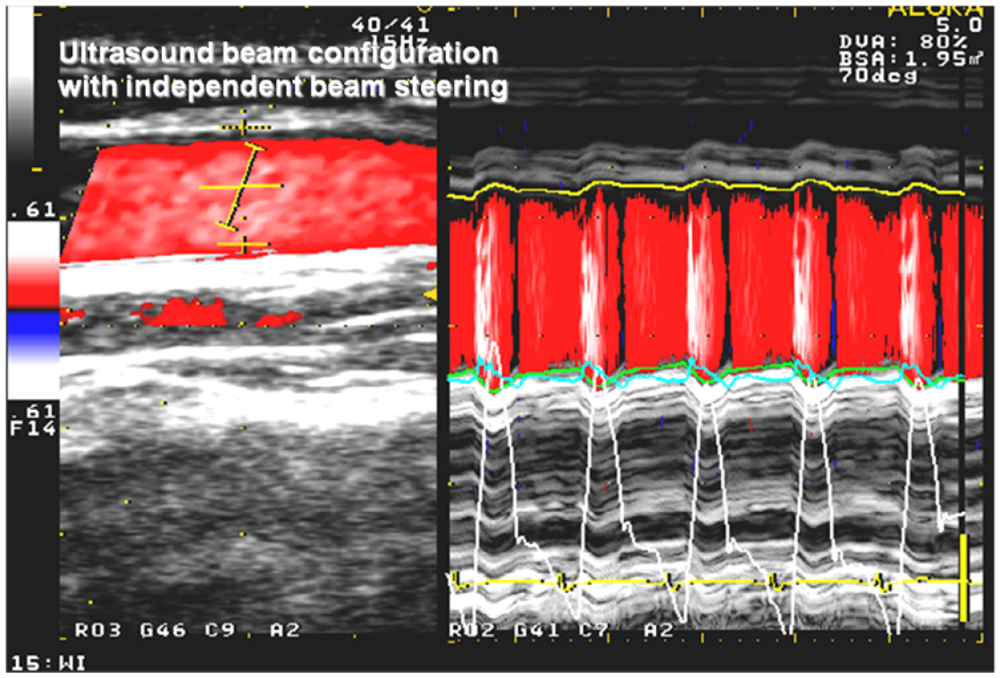

2.3. Echocardiography

3.3. Wave Intensity Study